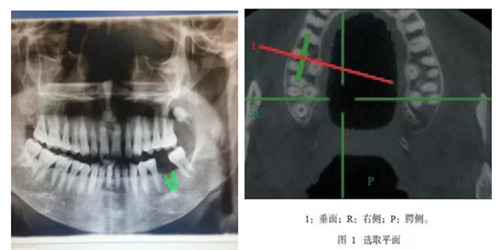

CBCT是一種錐形束投照計算機重組斷層影像設備,可用于種植、頜面外科、正畸、牙體牙髓病、牙周病等方面的檢查。通過口腔CT的立體影像可以全面了解頜骨形態、牙齒周圍的解剖結構,牙根的位置與形態、下頜神經管的走向和范圍、上頜竇底的位置及上牙牙根與上頜竇的關系、下牙牙根與下頜神經管的位置關系等肉眼不可見的組織結構。

CBCT具有特點:圖像分辨清晰、重建速度快速、重建時間低于15S,成像范圍合理、偽影校正技術獨特,避免重疊等,操作簡單便捷,一次掃描即可獲得全口腔雙牙列三維立體影像 等一系列特點。與傳統CT相比CBCT的輻射量更低、牙齒與頜骨成像更加清晰。我院CBCT附送患者一張影像刻錄光盤,觀看膠片不需要觀片燈,直接在醫生電腦上即可動態觀看圖像;消除患者等待煩惱。